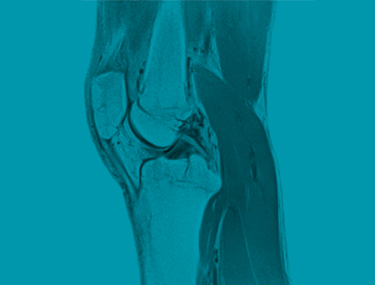

Definition: Im Unterschied zum konventionellen Röntgen arbeitet die Kernspintomographie mit starken Magnetfeldern, weswegen mit dieser Methode andere Strukturen als im herkömmlichen Röntgenbild sichtbar gemacht werden können. Gerade auch im Bereich der Sportmedizin ist deswegen diese Methode inzwischen zum unverzichtbaren Standard bei der Abklärung von Sportverletzungen geworden.

Das MR liefert auch bildgebende Information über Weichteile. Gerade im Gelenksbereich werden neben dem knöchernen Skelett auch Strukturen wie Bandapparat, Sehnen, Gelenkskapsel, Knorpel, Meniscus, Muskel bildhaft in mehreren Ebenen abgebildet. Ebenso können bei Unfällen verletzungsbedingte Flüssigkeitsansammlungen wie bei Gelenkserguss und Schwellung durch Einblutung im Weichteilmantel dargestellt werden. Ein Quantensprung in der prezisen Findung einer Diagnose – damit wird bei Verletzungen im Gelenksbereich das MRI zum Goldstandard in der Sportmedizin.